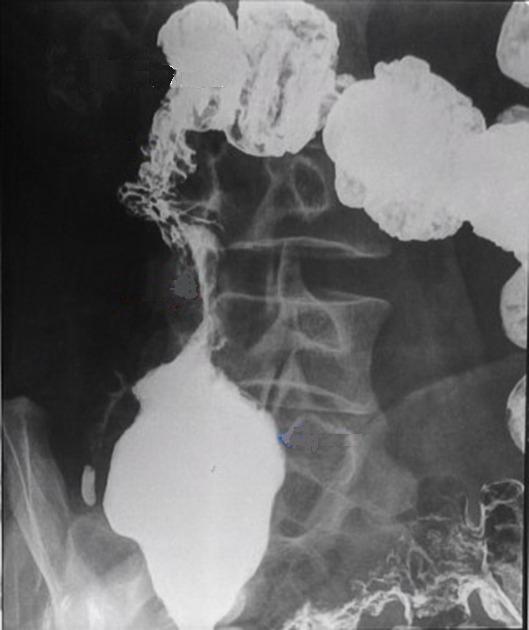

Aspect

deformation de la region ileocaecale avec

retrecissement de ileon . Image radiologique de

lavement baryte mono de contrast |

Image de retrecissement et deformation de

la region ileo-caecale . La valvule ileocaecale est

fixe , rigidite et incompetance . Tuberculose

ileocaecale . Image radiologique en mono de contrast